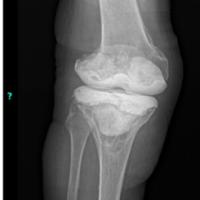

Subcutaneous emphysema (SE) involves the presence of air or gas within the subcutaneous tissue [1]. It can result from various sources, including surgical procedures, trauma, infections, or spontaneous events [1,2]. While SE in the hand and upper extremities following minor trauma is rare, it has been reported in a few clinical cases [1,3,4,5,6,7,8,9]. Healthy patients with minor trauma-induced SE, as presented in this case, typically do not warrant intensive or surgical treatment. Most patients with uncomplicated traumatic SE can be effectively managed with conservative treatment, including proper wound care and antibiotics [1,10]. This approach is recommended for patients who are systemically stable, have minimal pain, and show no signs of extensive cellulitis [9,11]. However, consideration for necrotizing fasciitis (NF) must be made through a thorough review of the patient’s history, clinical examination, and evaluation of the Laboratory Risk Indicator for Necrotizing Fasciitis (LRINEC) score, clinicians can guide management appropriately and prevent unwarranted surgical intervention in a high-stakes diagnosis [1,12]. The LRINEC score, developed by Wong et al. in 2004, uses six laboratory values – C-reactive protein (CRP), total white blood cell (WBC) count, hemoglobin (Hgb), sodium, creatinine, and glucose – to stratify patients into low, medium, or high risk for NF [12,13]. A score of 6 or more is concerning, while a score above 8 is highly predictive of the disease [1]. Distinguishing SE from more severe conditions, such as NF, is critical due to the rapid progression and potential for extensive damage involving the skin, fascia, subcutaneous tissues, and muscle [1]. This condition is frequently associated with an external injury that introduces skin or environmental pathogens into the deeper soft tissue layers [14]. The presence of acute swelling with crepitus on physical examination and subcutaneous gas seen on radiographs suggests a necrotizing soft tissue infection (Fig. 1) [14,15]. The incidence of NF is estimated to range from 0.3 to 15 cases/100,000 people [16].

Figure 1: Anteroposterior and lateral of the right forearm radiographs revealing soft tissue gas from the first and second webspace going proximal up the volar and lateral forearm.